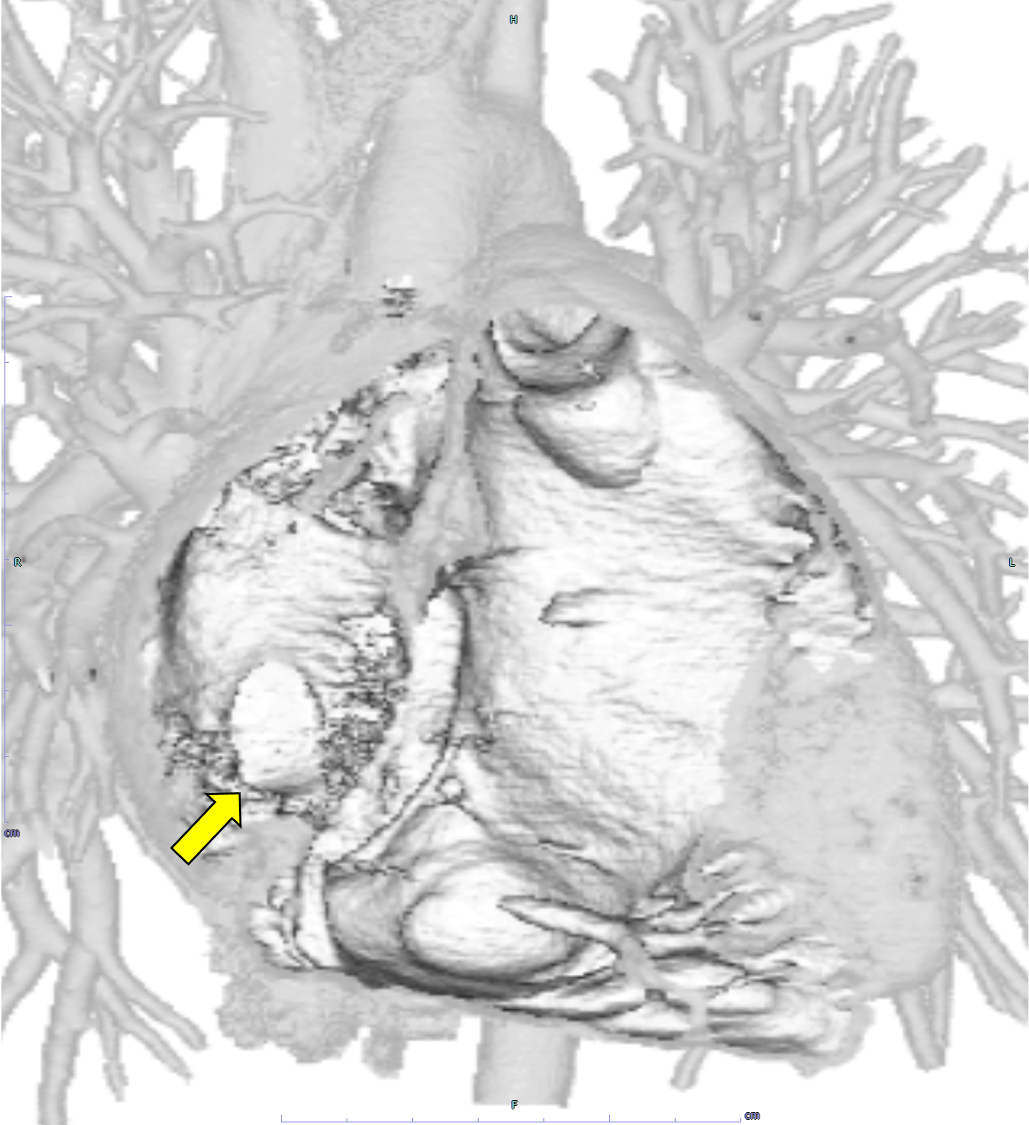

図3.心電図同期造影CTボリューム・レンダリング画像(動脈相)

右下肺静脈は右心房直下の下大静脈および左心房に流入している。(矢印)

図4.心電図同期造影CTボリューム・レンダリング画像(動脈相)

25×15mm大の欠損孔を認める。(矢印)